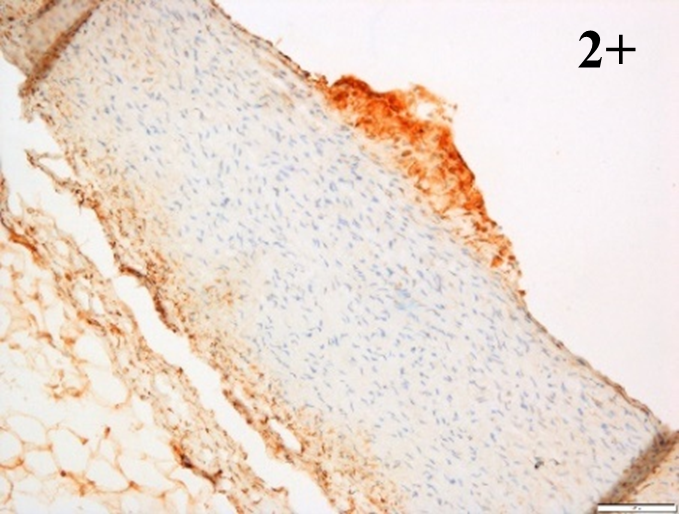

According to the percentage endothelial staining of cells, semi-quantitative

scores were applied. Score: 0 (negative); 1+ (1–10% positive cells); 2+

(11–25% positive cells) and 3+ (

Medium to high expressions of adhesion molecules, such as ICAM-1, VCAM-1 and

e-selectin were observed in the aortas of rabbits fed with HCD. This represents

the initiation of the lesion stage, where the endothelial cells have been

stimulated by the ox-LDL to express the adhesion molecules, which could lead to

the recruitment of monocytes and transmigrate into the intima by diapedesis as

well as differentiate into pro-atherogenic macrophages [47]. An increased

expression of pro-inflammatory biomarkers, such as IL-6, IL-8 and NF-